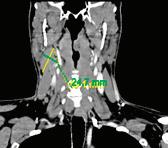

подготовка на пациента за кардиохирургична оперативна интервенция в обем 3 аорто-коронарни байпаса. От проведената КТ се установява хетероденсна формация на ниво II шиен лимфен колектор, с размери 13/18 мм. От анамнезата няма данни за болка, дисфагия, диспнея или дисфония. При наблюдение в следоперативния период се отчита постепенно нарастване на размера на формацията.

Поради динамика в локалния статус пациентът се насочва за консултация и последващо лечение в УНГ клиника, където от проведените образни изследвания (КТ, УЗД) се на -

блюдава хетероденсна мекотъканна формация с размери 25/28 мм, наличие на кистични

зони в обема й и лифмни възли по съседство.

След ексцизионна биопсия, хистологията до -

казва масивна метастаза от умерено диференциран плоскоклетъчен карцином. Насоченото

чен източник.